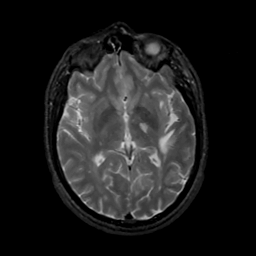

MR Study #10, April 28, 1991 -- Slice #25